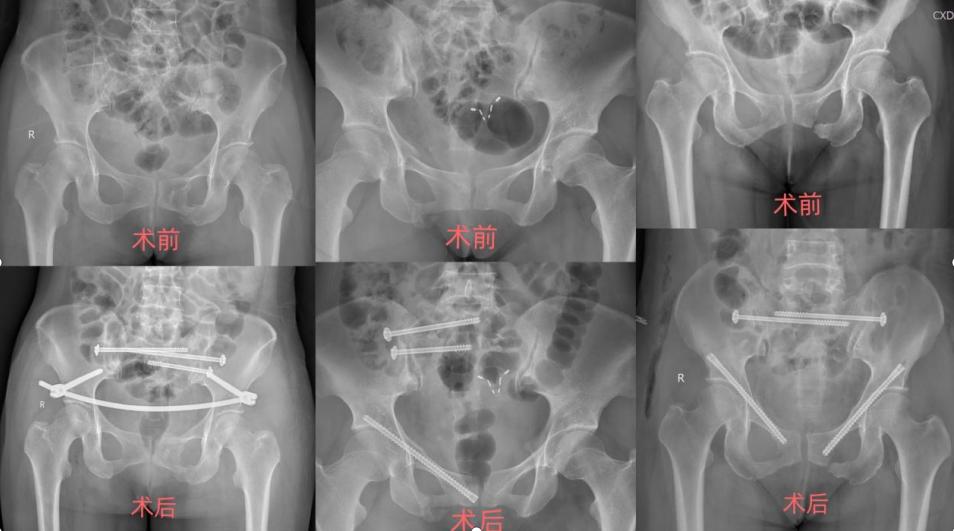

我院成功实施S2AI螺钉内固定技术 一对长钉子解决老人腰痛腿麻下肢瘫 2021-11-02 近日,绵阳市第三人民医院疼痛科脊柱外科成功为一名腰椎骨质破环患者实施了骶2-髂骨(S2AI)螺钉内固定术,重建腰骶稳定性。63岁的唐大爷前段时间感觉腰部连带着下肢疼痛、麻木,尝试按摩理疗、药物治疗后,症状不断没有缓解,近2个月症状进行性加重,到我院疼痛科脊柱外科求诊…